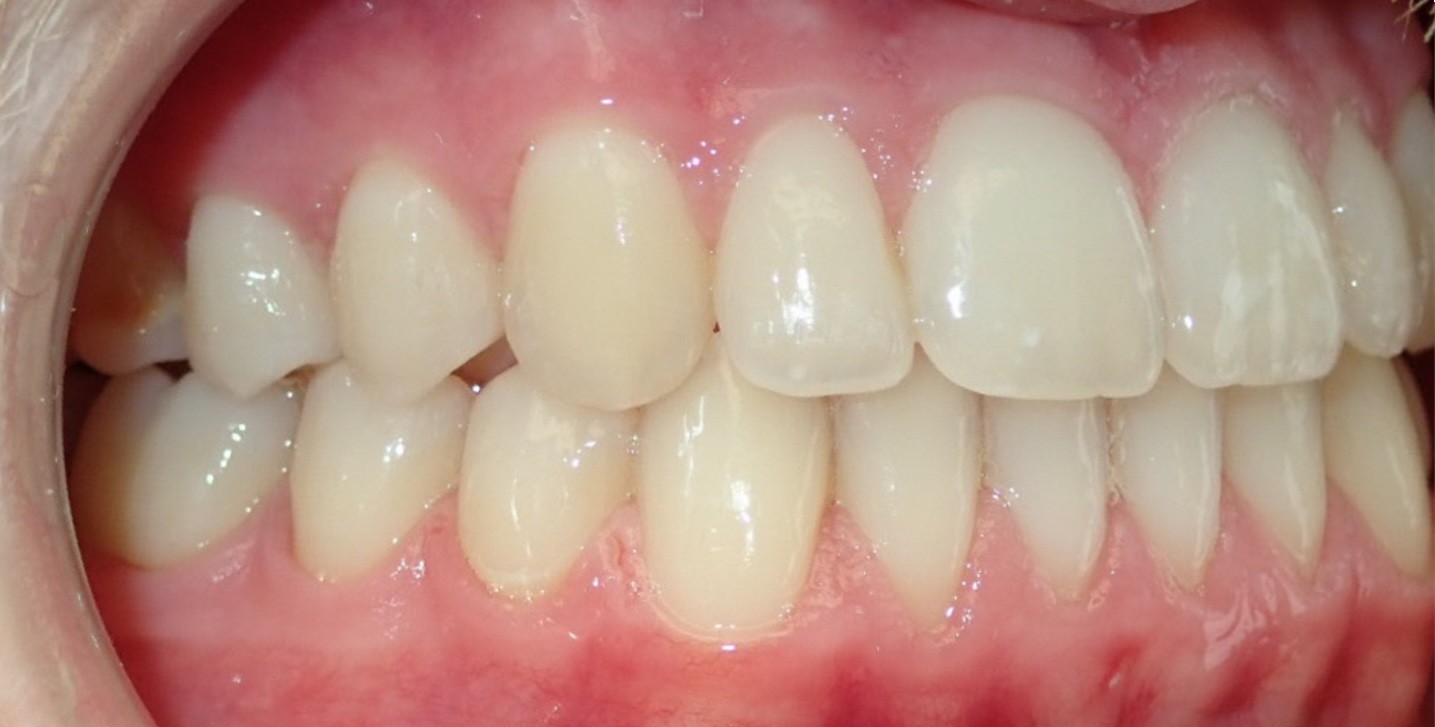

Initial treatment

INTRAORAL